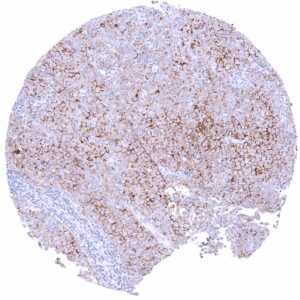

| Spleen | Strong membranous CD35 staining of most cells in the white pulpa. | |

In normal tissues, CD35 is most highly expressed in normal follicular dendritic cells, but it can also be seen on lymphocytes of various types, macrophages, granulocytes, and erythrocytes.

| Tonsil | Strong membranous CD35 staining of follicular dendritic cells and of a subset of lymphocytes. The squamous epithelium is CD35 negative. | |